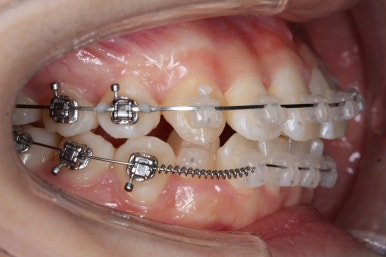

교정장치 : 자가결찰 세라믹(데이몬 클리어) + 미니스크류

연산동교정치과에서 이번에 진행한 방법은 비발치교정이기 때문에 미니스크류를 잇몸뼈에 식립합니다.

위 사진에서 화살표 부분이 미니스크류인데요.

어금니쪽 잇몸에 아주 작은 나사가 보이실텐데요. 이것을 이용해서 전체 치열을 뒤로 당겨넣습니다. 물론 사랑니는 제거가 된 상태입니다.